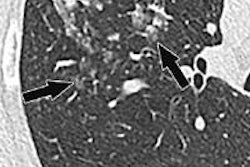

Chest CT scans were performed on 16- and 64-detector-row scanners from GE Healthcare and Siemens Healthcare. The images were reviewed by board-certified radiologists, and the group further looked at the finding in relation to the reason for the recommendation.

Insignificant findings at CT were seen in an additional 20% of cases, and about 38% contained no corresponding abnormalities. At the same time, newly diagnosed, biopsy-proven malignancies were found in 8.1% (56 of 691) cases that underwent follow-up CT.

In all, 41 of the 56 biopsy-proven malignancies were lung cancer (including 27 adenocarcinoma, five squamous cell carcinomas, two non-small cell carcinomas, and six small cell carcinomas), Alkasab said. There were 12 lung metastases, three mediastinal lymphomas, and two Hodgkin's lymphomas in the mix as well.